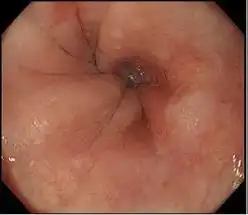

光学85X放大倍数

该范围放大图像85x*2,其高清图像质量轻松提供粘膜表面的视图。结合更明亮的NBI(窄带成像),粘膜组织和毛细血管网络得到增强,进一步支持详细观察。

白光 用NBI光学放大85x